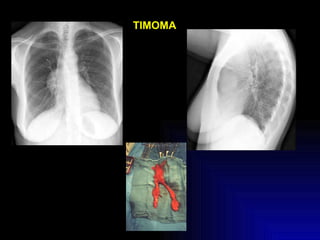

Timectomia No se practica en la MG ocular. No se realiza después de los 60 años (a menos que haya timoma). Requiere preparación. Mejores resultados en mujeres jóvenes. Se prefiere abordaje transesternal.

TIMOMA